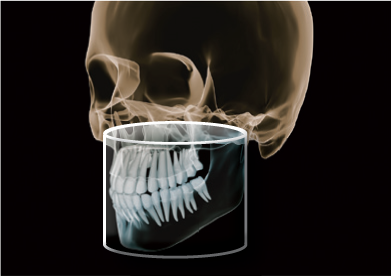

Z najnowszym aparatem Orthophos SL 3D, Twoja praktyka będzie przygotowana na każdy rodzaj leczenia. Przełomowa technologia sensora panoramy DCS oraz funkcja

Sharp Layer – zaspokoją potrzeby lekarzy, którzy wymagają maksimum szczegółów z obrazu panoramicznego. 3D daje Ci wybór pomiędzy objętością 11 cm x 10 cm, obrazująca pełne łuki szczęki i żuchwy wraz z sąsiadującymi strukturami, a 8 cm x 8 cm dająca wystarczającą ilość informacji diagnostycznych dla lekarzy ogólnych i implantologów.